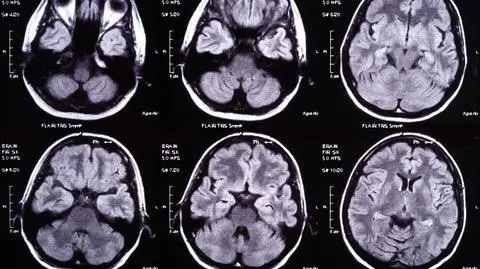

Badaniom poddano 3744 hospitalizowanych, dorosłych pacjentów z COVID-19. Problemy neurologiczne pojawiły się u około 80 procent przebadanych. 37 procent pacjentów zgłosiło problem bólu głowy, a 26 proc. straciło węch lub smak.

Zajmujący się tymi pacjentami lekarze stwierdzali ostrą encefalopatię (uszkodzenie mózgowia) u prawie połowy hospitalizowanych (49 proc.). Dla porównania - encefalopatia dotyka 17 proc. pacjentów będących wcześniej w śpiączce i sześciu proc. tych, którzy przeszli udar mózgu.

Wbrew wcześniejszym obawom, koronawirus nie atakuje mózgu bezpośrednio. Opuchnięcie i zapalenie opon mózgowych występowało bardzo rzadko i dotyczyło zaledwie jednego procenta hospitalizowanych.

- Ostra encefalopatia jak dotąd występowała najczęściej. Pacjenci mają zmienne doznania sensoryczne lub ograniczoną świadomość. Innymi objawami są: zdezorientowanie, majaczenie i nadpobudliwość - wylicza Chou, dyrektor Pitt Safar Center for Resuscitation Research.